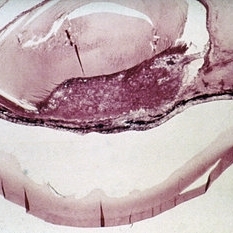

Slide 7-21

Feb 25 2019 by Lancaster Course in Ophthalmology

Squamous cell carcinoma of the conjunctiva may present as an exuberant tumor mass.

Condition/keywords: conjunctiva, tumor